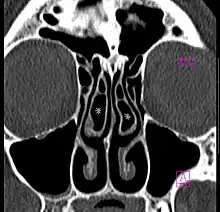

Large concha bullosa